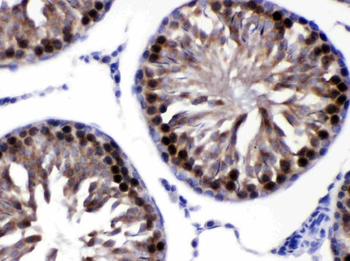

−| Tested Applications | ELISA, IHC |

| Dilution Range | IHC-P:1:20-1:200 |

| Immunogen | Recombinant Human Protein S100-A6 protein (1-90AA) |

| Target | S100A6 |

S100A6 Antibody (orb239280)